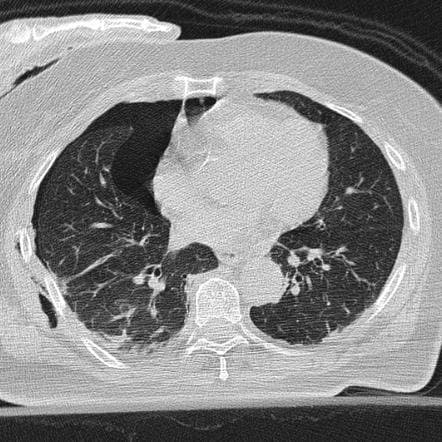

Figure 2: Traumatic Pneumothorax, Case courtesy of Dr David Cuete, Radiopaedia.org, rID: 24619, https://radiopaedia.org/cases/24619